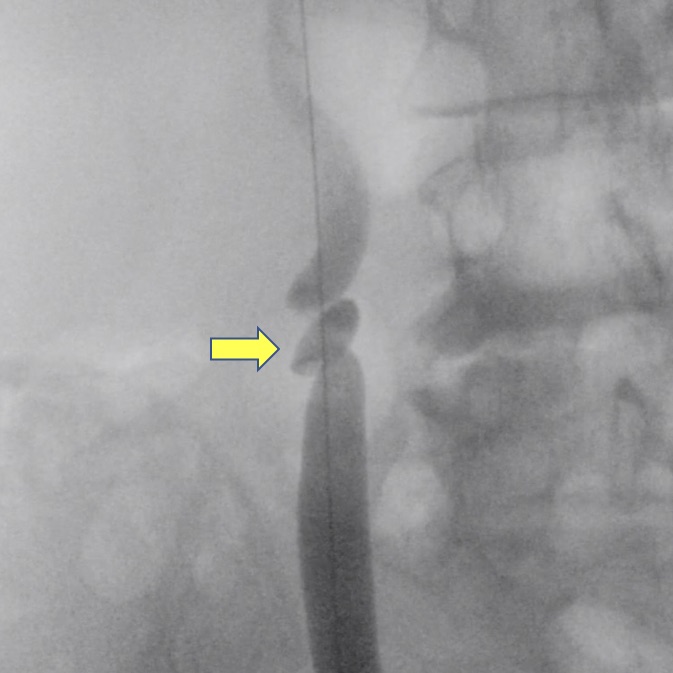

La cirugía se inicia con la instalación de un catéter ureteral externalizado. Éste permite contrastar la vía urinaria superior e identificar en la fluoroscopía, la pelvis y los cálices del riñón a tratar. Posteriormente se realiza una punción renal bajo rayos y/o dirigida por ecografía, hacia la papila renal del cáliz escogido para ingresar. Obtenido este acceso, se avanza una guía hidrofílica y se procede a la dilatación del trayecto percutáneo, lo que permitirá la instalación de una camisa (amplatz) que comunicará la piel con el cáliz y dará acceso al nefroscopio, equipo operado por el urólogo para la fragmentación y extracción de la litiasis a tratar.